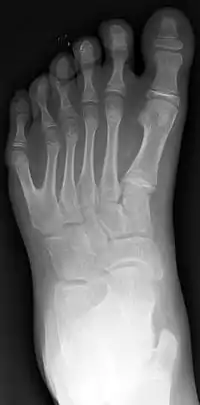

Polidactilia

La polidactilia (del griego poly, ‘muchos’ y daktylos, ‘dedo’) es un trastorno genético donde un humano nace con más dedos en la mano o en el pie de los que le corresponde (normalmente un dedo más). Se detecta en el momento del nacimiento. A estos dedos se les llama «dedos extra» o «dedos supernumerarios».

El dedo adicional es generalmente un pequeño pedazo de tejido fino y suave. A veces contiene el hueso sin articulaciones; ocasionalmente el dedo se encuentra completo y funcional. El dedo extra suele ubicarse tras el meñique de la mano o del pie, es menos frecuentemente del lado del pulgar e inusualmente intercalado entre otros dedos. Suele ser una bifurcación de un dedo normal, y rara vez nace de la muñeca como los demás dedos.